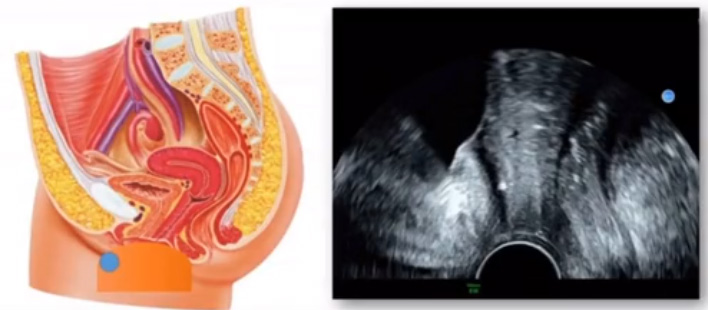

位于輸卵管的后下方,子宮兩側(cè)的后上方;借卵巢系膜與子宮闊韌帶后層相連。正常成人卵巢約4x3x2cm,跟睪丸的數(shù)值差不多,都是性器官,絕經(jīng)后卵巢萎縮變小、變硬。所以絕經(jīng)后婦女很難找到卵巢,主要功能:生殖和內(nèi)分泌功能分泌性激素。女性的第二性征。女性內(nèi)生殖器的血管分布,動脈有子宮動脈,卵巢動脈,陰道動脈,陰部內(nèi)動脈。靜脈它是與動脈伴行。重要了解的是子宮動脈,子宮動脈是髂內(nèi)動脈前干的重要分支,妊娠時(shí)候血流速度會增加的,為無創(chuàng)性檢查胎盤血管阻力的方法。未孕期頻譜為高阻力低舒張波形;正常妊娠時(shí)血流速度增加,血流阻力下降。